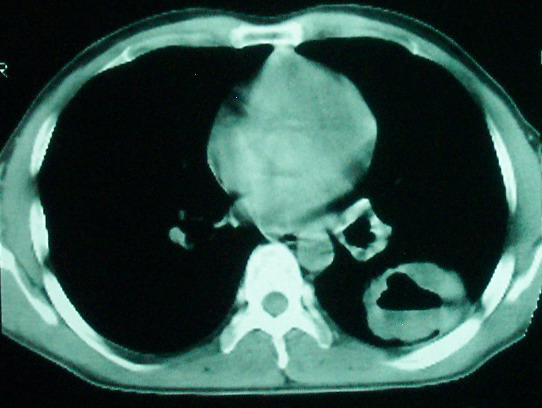

m      37y      发热   咳脓痰月余      ct肺脓肿但住院抗炎治疗后双肺内结节不知该如何解释

治疗后见左肺下野病灶较前缩小但双肺内结节影似无变化请较各位老师该如何下结论    治疗前wbc14.5 治疗后wbc 11.0

血源性肺脓肿,一般由原发感染灶引起脓毒败血症,在肺部形成小脓肿,病变变化快,容易形成肺气囊,脓气胸,主要与转移瘤鉴别,通过临床病史可分

结合病史考虑血源性肺脓肿,与转移瘤鉴别

1、左下肺鳞癌伴两肺及纵隔淋巴结转移;

2、两上肺支扩伴慢性炎症。

左下肺病灶除了明显的厚壁空洞 气液平外,明显见壁结节,另两肺多发小结节,综合考虑:左下肺周围性肺癌伴肺内转移.

如果你仔细的同层面对比,你会发现所有的病灶均有比较明显的吸收、缩小。病变的形态,特别是脓肿的形态、壁的厚薄、内壁均有很大的变化,均在往好的方面发展。与临床症状、血像均符合,治疗效果比较显著,就是肺脓肿并双肺的化脓性炎症灶。